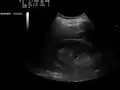

Ultrasonographic view of the abdomen demonstrating fluid within Morison's pouch